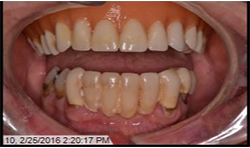

A 69-year-old male presented with an existing maxillary full denture and mandibular fixed partial denture (Tooth Nos. 22-27) with pain and suppuration on abutment teeth supporting the FPD (Figs. 7, 8). All existing abutment teeth were carious and periodontally involved. It was decided with the patient the best treatment option would be to extract the remaining mandibular teeth. All options were presented to patient and patient desired a fixed hybrid for both arches.

Fig.7